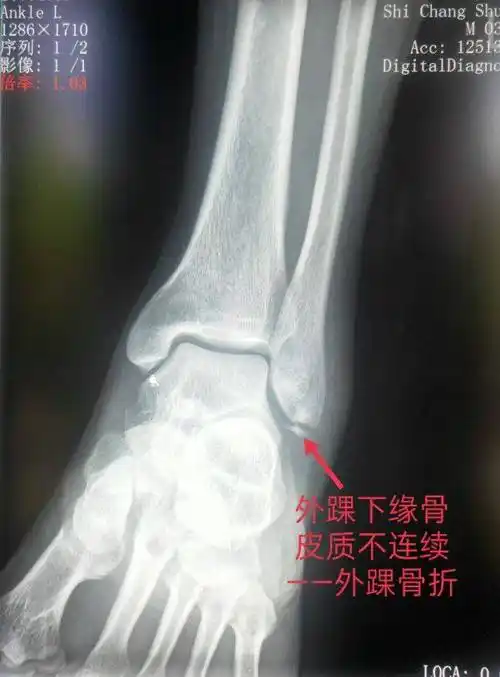

【读片】右踝外伤